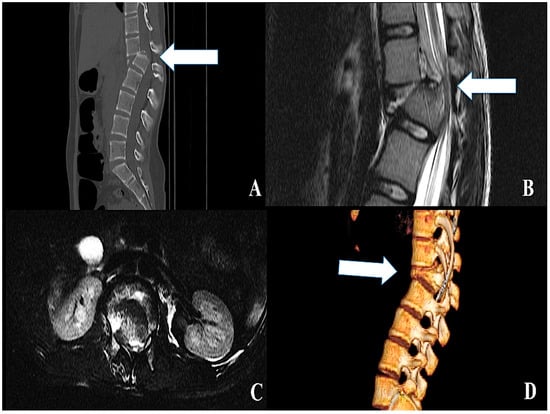

2.1. Traumatic SCI: Clinical Findings